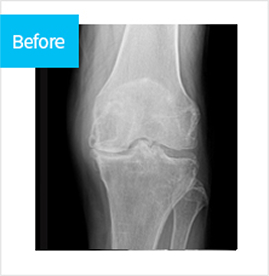

치료 전 붉게 패여 손상된 연골이 치료 후 정상적으로 회복된 모습

before img after img